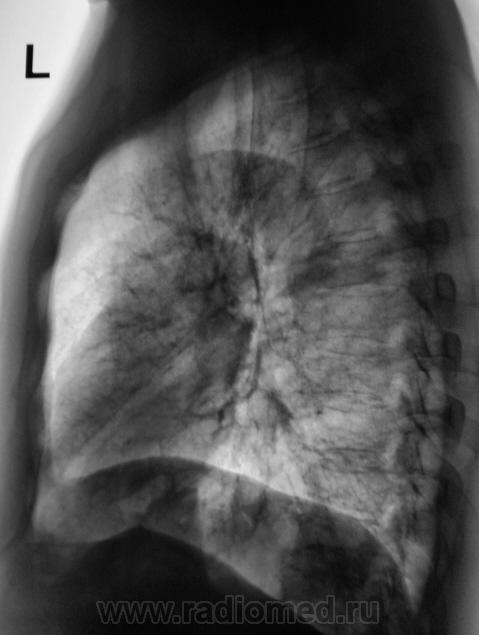

При расшифровке флюорограмм пациент "взят на контроль". Жалоб пациент не предъявляет. Подняли "архив", флюорограмма за 2009 г. - "норма".

Произвели стандартное дообследование.

Томограммы.